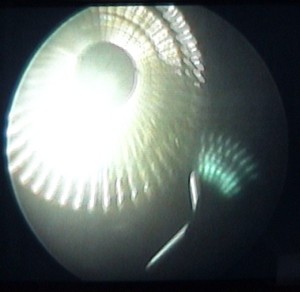

enlèvement d'un ménisque |